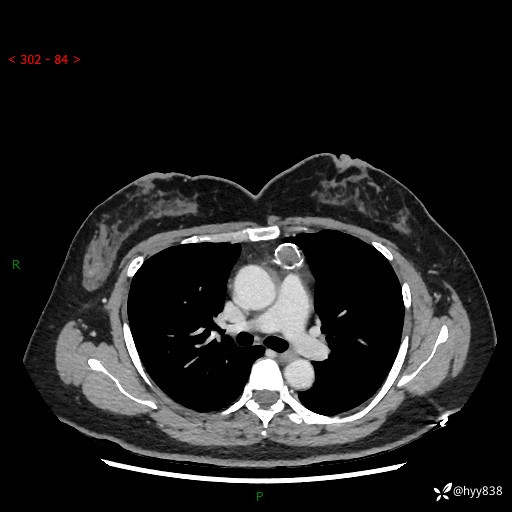

中年女性,检查发现纵隔占位3月余。圆圆的肿物,周围环绕一圈钙化---结果公布~

现病史:患者于3月前体检行胸部CT检查发现纵隔占位,患者平素无明显咳嗽咳痰,无心慌、胸闷、胸痛、呼吸困难、低热、盗汗,无头痛、头晕,无腹痛、腹胀等不适。现患者欲求进一步治疗,遂来我院就诊,以“纵隔占位”收入我科。 患者自起病以来,精神可,睡眠可,饮食可,大小便正常,体重无明显改变。

胸部CT平扫+增强